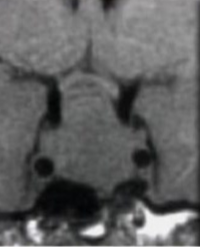

snowman configuration

what is the classic MRI sign of a pituitary macroadenoma on MRI?

snowman (pituitary macroadenoma)